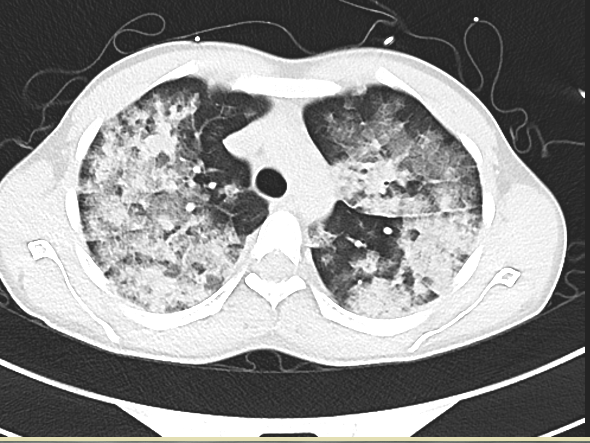

接診醫(yī)生在對小輝完善系列檢查后發(fā)現(xiàn):小輝血氧飽和波動僅有49%至60%(在不吸氧的條件下,正常血氧飽和度為95%以上),血壓為89/63毫米汞柱(血壓單位),脈率達(dá)每分鐘144次,呼吸每分鐘39次,雙肺滿布大量濕啰音,情況危急,隨時會有生命危險(xiǎn)。接診醫(yī)生立即聯(lián)系了心血管內(nèi)科,將小輝送至心血管內(nèi)科接受緊急救治。

大附院心血管內(nèi)科醫(yī)師憑著豐富的臨床經(jīng)驗(yàn),考慮小輝患的是急性肺水腫中極嚴(yán)重的急性高原肺水腫。小輝的病情隨時有迅速惡化的風(fēng)險(xiǎn),一旦得不到有效的救治,小輝即將面臨昏迷甚至死亡!他們當(dāng)即為小輝施行了系列緊急治療。經(jīng)過心血管內(nèi)科醫(yī)護(hù)人員齊心協(xié)力的救治后,小輝生命體征逐漸平穩(wěn),氧飽恢復(fù)到95%。

據(jù)大理大學(xué)第一附屬醫(yī)院院長、心血管內(nèi)科專家吳新華介紹,急性高原肺水腫是一種急性致命性非心源性肺水腫,也是嚴(yán)重高原病最常見的類型。急性高原性肺水腫的主要癥狀表現(xiàn)為突發(fā)性胸悶、氣喘、咳嗽、咳痰等,其發(fā)生機(jī)制主要為急性低氧引起肺動脈壓力過度增高、肺血管通透性增高、肺水清除障礙、液體潴留及體液轉(zhuǎn)運(yùn)失調(diào)。如果該病能得到及時診斷和積極治療,一般預(yù)后良好。解除病因、改善機(jī)體供氧是防治急性高原性肺水腫的首要措施,一旦延誤診斷和治療??芍滤?。(春城晚報(bào)-開屏新聞 記者劉文波 楊維琦 通訊員趙秋燕 大理大學(xué)第一附屬醫(yī)院供圖